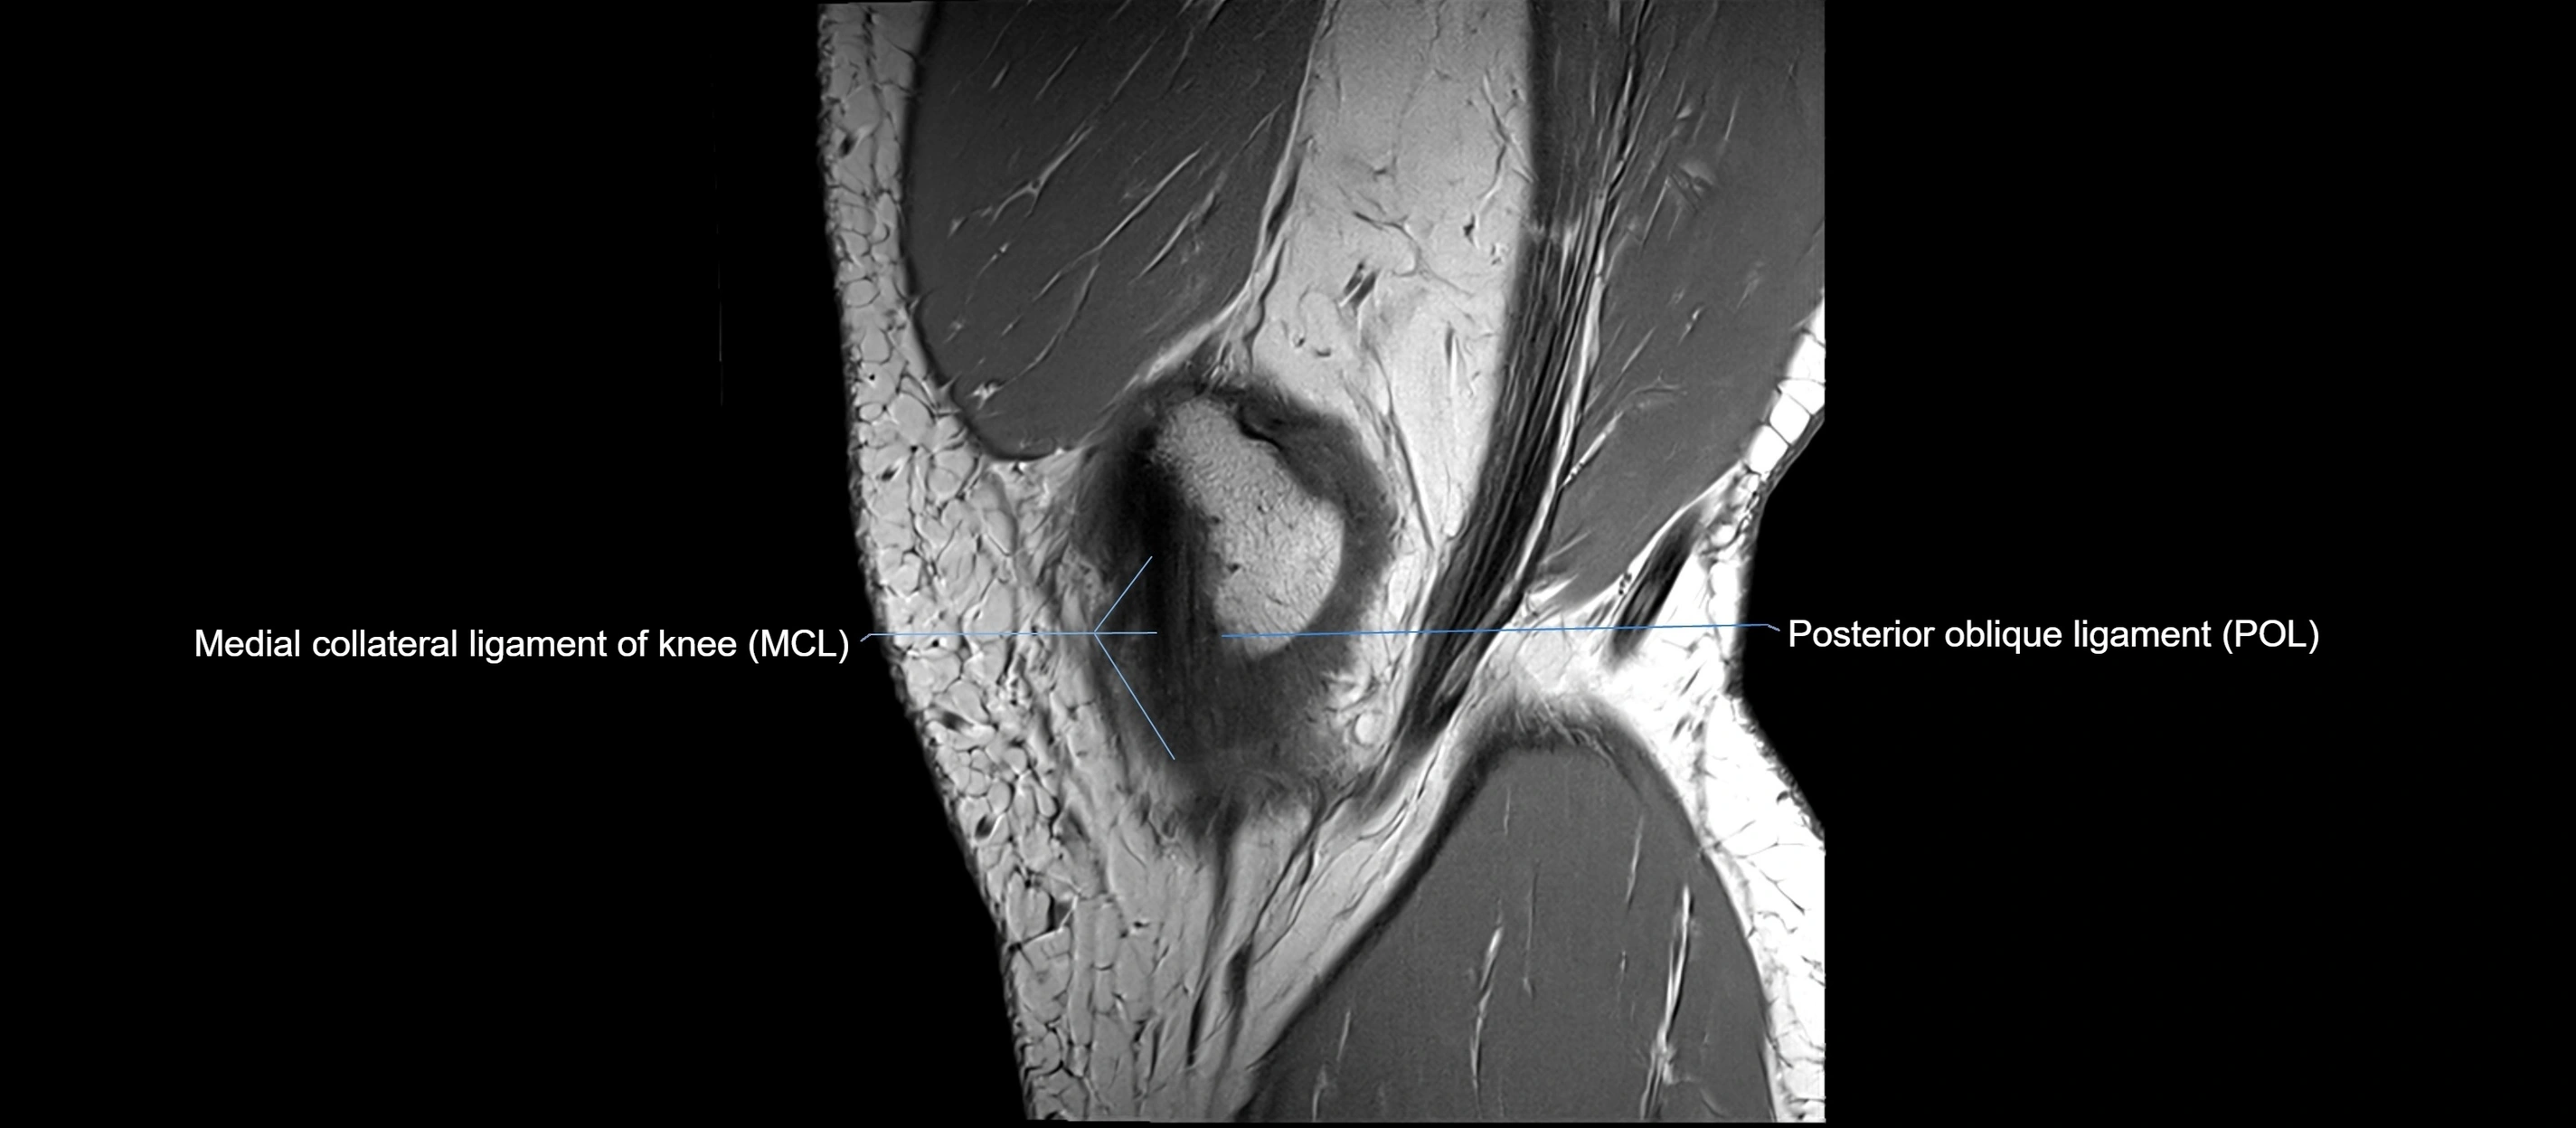

MRI images

image